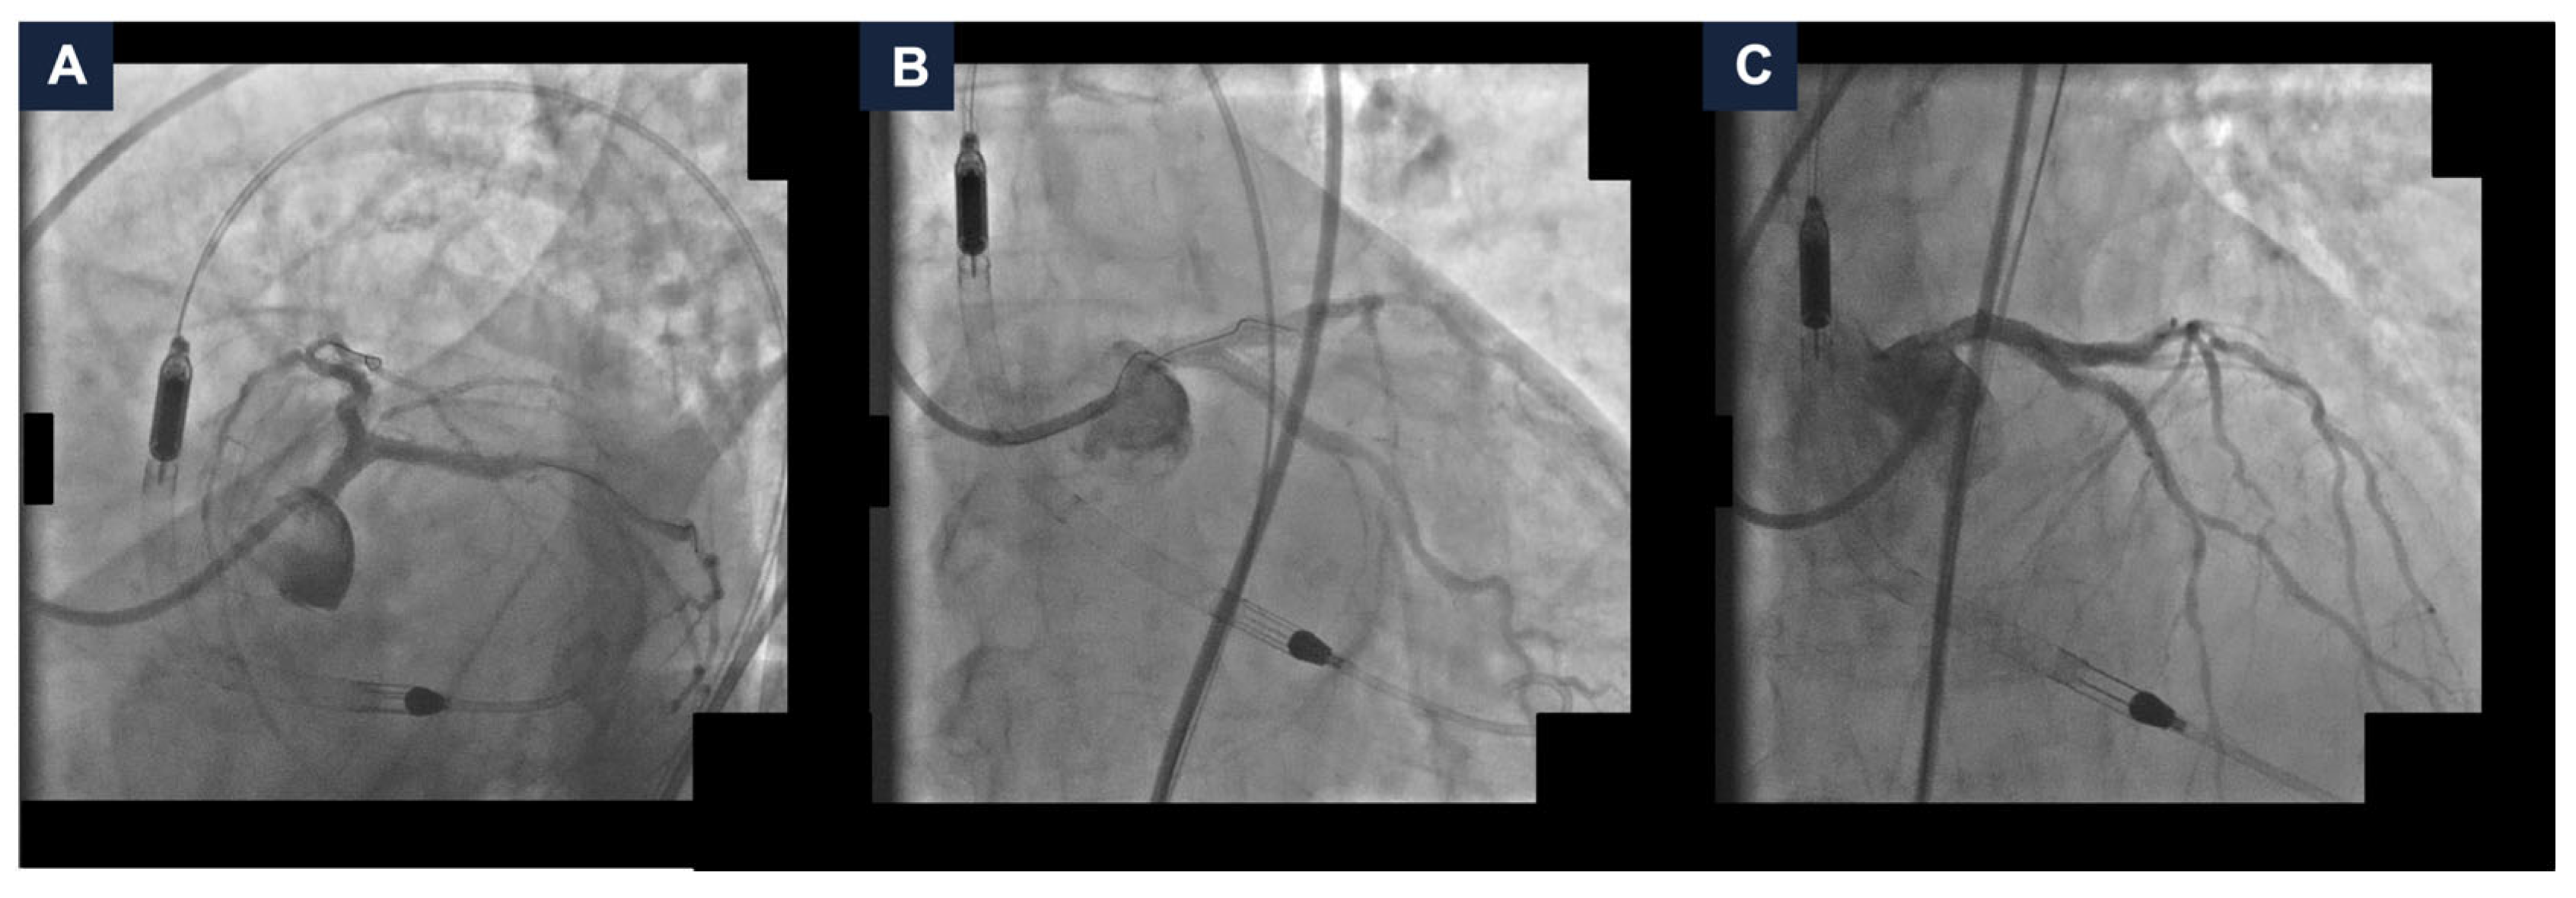

A 95-year-old man with hypertension and hyperlipidemia was admitted to our hospital with Non-ST-segment elevation myocardial infarction (NSTEMI). His medical history was positive for chronic obstructive pulmonary disease and stage IV chronic kidney disease (the estimated glomerular filtration rate (eGFR) at hospitalization was 28 mL/min/1.73 m2). No other relevant comorbidities were reported, and he had very good cognitive and geriatric conditions. Transthoracic echocardiography was performed and revealed a moderately hypertrophic left ventricle, akinesis of the apex and anterior interventricular septum, hypokinesis of the anterior and anterolateral walls, and a left ventricular ejection fraction (LVEF) of 33%; the right ventricle had normal dimensions with a tricuspid annular plane systolic excursion of 19 mm; the mitral and tricuspid valves had moderate regurgitation, and the estimated systolic pulmonary artery pressure was 40 mmHg. Coronary angiography was scheduled. It showed a dominant right coronary artery, with a good development and caliber, and no critical stenoses. The left coronary artery had a good caliber and development, too. It presented a heavily calcified, critical stenosis of the ostial left main coronary artery (LMCA), along with multiple, severely calcified, sub-occlusive stenoses of the ostial left circumflex artery (LCx) and the proximal left anterior descending artery (LAD), and several, highly calcified, critical stenoses of the mid LAD and proximal LCx (Figure 1, panel A–C and Video S1). After the coronary angiography, a comprehensive clinical and technical evaluation of the patient’s conditions was performed, in order to determine the best therapeutic and prognostic strategy. The most relevant clinical and technical elements were as follows: the patient’s very active lifestyle, with no relevant clinical comorbidities that could have given him an unfavorable prognosis; the multiple, heavily calcified, sub-occlusive and critical stenoses of the LMCA-LAD-LCx bifurcation, that had a strong prognostic impact; and the severely depressed systolic function of the left ventricle, which conferred to the revascularization an even higher risk. MCS-assisted PCI of the LMCA-LAD-LCx bifurcation was proposed, in order to offer a prognostic benefit. The patient initially refused. Therefore, the hospitalization was extended in order to optimize the medical therapy. Antihypertensive agents (Amlodipine, Bisoprolol, and Doxazosin) and diuretics (Furosemide and Canrenone) were titrated while renal function and serum potassium levels were monitored to ensure safety and efficacy. Thus, the patient was discharged on a dual antiplatelet therapy with Ticagrelor 180 mg/day and Acetylsalicylic Acid 100 mg/day, Amlodipine 10 mg/day, Bisoprolol 5 mg/day, Furosemide 50 mg/day, Canrenone 50 mg/day, Doxazosin 8 mg/day, and a dual hypolipidemic therapy with Atorvastatin 20 mg/day and Ezetimibe 10 mg/day (at hospital discharge, the eGFR was 25 mL/min/1.73 m2). Two weeks later, due to persistent refractory angina at rest, the patient agreed to proceed with the scheduled intervention and was readmitted. At the time of the second hospitalization, the eGFR was 16 mL/min/1.73 m2; consequently, Canrenone was suspended.

Figure 1.

Baseline coronary angiography. (A) Right coronary artery angiography demonstrating no critical stenoses. (B,C) Left coronary artery angiography in cranial (panel B) and caudal (panel C) views showing severe, heavily calcified, sub-occlusive and critical stenoses of the left main coronary artery, proximal and mid left anterior descending artery, and ostial and proximal left circumflex artery.